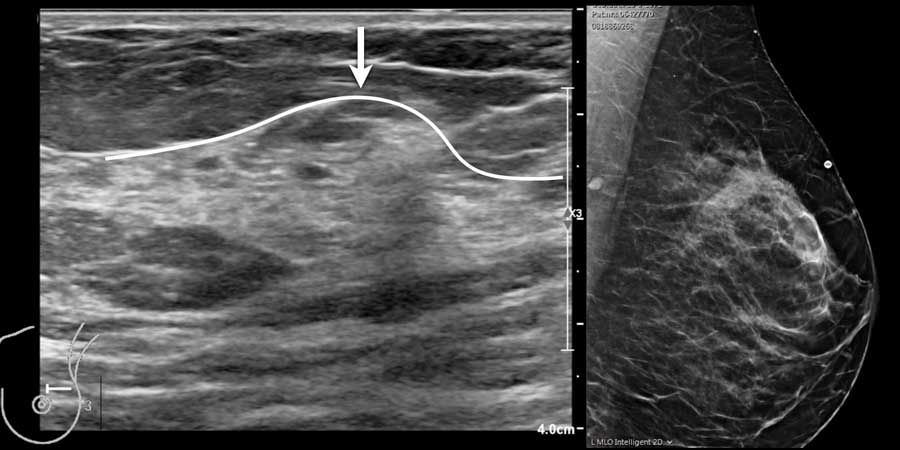

Trong cùng một tuyến vú có thể tồn tại các vùng có nhiều mô mỡ xen kẽ với các vùng chủ yếu là mô xơ tuyến, như có thể thấy trên video.

Khi quan sát đường bờ của mô tuyến (mũi tên), có thể hình dung rằng khi sờ nắn sẽ cảm thấy gồ ghề và đôi khi tạo cảm giác như có một khối u khi mô tuyến rất phát triển.

Mô tuyến sờ thấy được

Mô xơ tuyến không phân bố đều trong vú và thường tập trung nhiều hơn ở góc phần tư trên ngoài.

Đôi khi sự phì đại khu trú của mô tuyến có thể rất rõ rệt, tạo thành một khối u mà khi sờ nắn không thể phân biệt được với khối u thực sự.

Hình ảnh siêu âm cho thấy một vùng tập trung mô tuyến nằm trong nền mô mỡ của vú.

Do mô tuyến có độ chắc hơn mô mỡ, vùng này sẽ có cảm giác như một khối khi sờ nắn.

Chụp nhũ ảnh được thực hiện với đánh dấu vị trí khối sờ thấy và cũng cho thấy hình ảnh tập trung khu trú của mô tuyến bình thường.

Video ghi lại trường hợp một phụ nữ tự phát hiện khối u ở vú.

Trên siêu âm, phát hiện mô tuyến phát triển rõ rệt.

Do mô tuyến có độ chắc hơn mô mỡ xung quanh, có thể hình dung rằng khi trượt ngón tay trên bề mặt da, vùng này sẽ có cảm giác như một chỗ gồ lên.